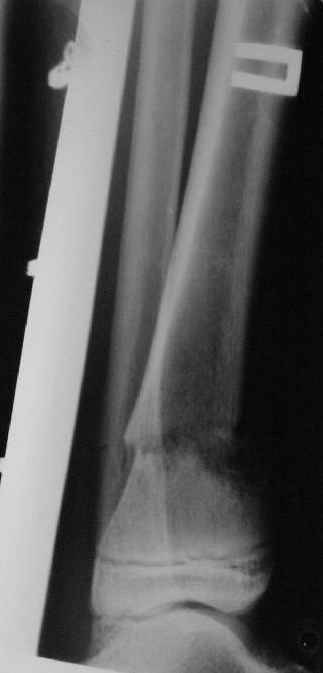

Операции: 1 Клиновидная резекция на вершине деформации м\берцовой кости.

2 Тугоподвижный ложный сустав н\3 б\берцовой кости. Рубцы выполняющие пространство между отломками, канал проксимального отломка иссечены.

Одномоментное устранение деформации, остеосинтез Г-образной пластиной.

Заживление проксимальной части раны вторичным натяжением без нагноения. Рана зажила. Спицы удалены через 1,5 недели после операции.

Учитывая фон (интеллект, etc) гипсовая повязка.

На данный момент ходит при помощи костыля (без присмотра -без костыля :), разрабатывает движения в г\стопном суставе.

Нашел в комп-ре схожий случай:

1) з/репозиция, 2) фиксация 2 спицами, 3) аппарат, 4) фиксационные

спицы удалены...

См. аттачт.

А можно было наложить аппарат и по поводу ложного сустава...

По крайней мере не было бы укорочения (пусть и в 2 см)...